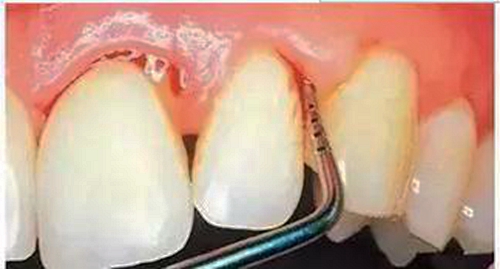

第三步:深齲

當您進食時,沒法咬食物,您說:“還好,可以用另外一邊牙齒咬。”

牙醫(yī)告誡說:“病變已經(jīng)破壞到了牙本質(zhì)深層,牙齒有較深的齲洞,溫度刺激,化學刺激以及食物進入齲洞時均引起疼痛,此時,及時做充填治療的話還來得及保住牙髓。”